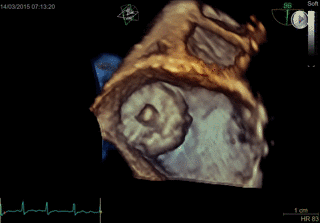

TAVI

- Paravalvular Leak After Transcatheter Aortic Valve Replacement. The New Achilles’ Heel? A Comprehensive Review of the Literature - https://www.ncbi.nlm.nih.gov/pubmed/23375925

- Aortic regurgitation after transcatheter aortic valve implantation: mechanisms and implications. http://cdt.amegroups.com/article/view/1552/2256

- 5-year outcomes of transcatheter aortic valve replacement or surgical aortic valve replacement for high surgical risk patients with aortic stenosis (PARTNER 1): a randomised controlled trial - https://www.ncbi.nlm.nih.gov/pubmed/25788234